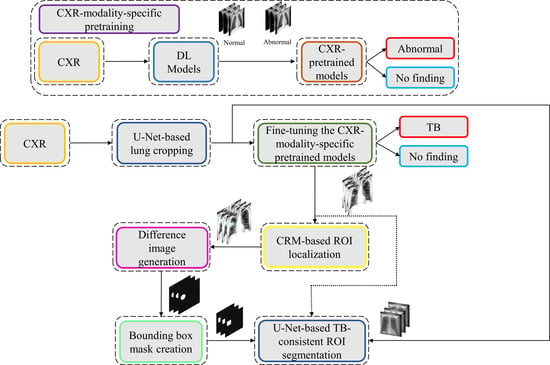

The process workflow toward CXR modality-specific pretraining and fine-tuning is illustrated in

Figure 5.

2.10. Task-Appropriate Data Augmentation: Augmenting Training Data with Weak Localizations to Improve TB-Consistent ROI Segmentation

The binary masks obtained from weak TB-consistent ROI localizations using the best-performing fine-tuned model and their associated CXR images are used to perform AT of the models used in

Section 2.7 toward improving TB-consistent ROI segmentation. The performance with such AT is evaluated with the test set derived from TBX11K training distribution and individually with the cross-institutional Shenzhen TB CXR-Subset-2 and Montgomery TB CXR data collections. We used a fixed seed value toward allocating 10% of the training data toward validation. Variability is introduced into the training process by augmenting the training data through affine transformations, including horizontal flipping, height and width shifting, and rotations. Callbacks are used to store model checkpoints, and the best performing model is used to segment TB-consistent manifestations. The predicted masks are overlaid on the original CXR input to localize the TB-consistent ROI boundaries. The performance of the models with AT is evaluated and compared to those with non-augmented training using confusion matrix, IOU, Dice, and AP@[0.5:0.95] metrics. We used a Windows